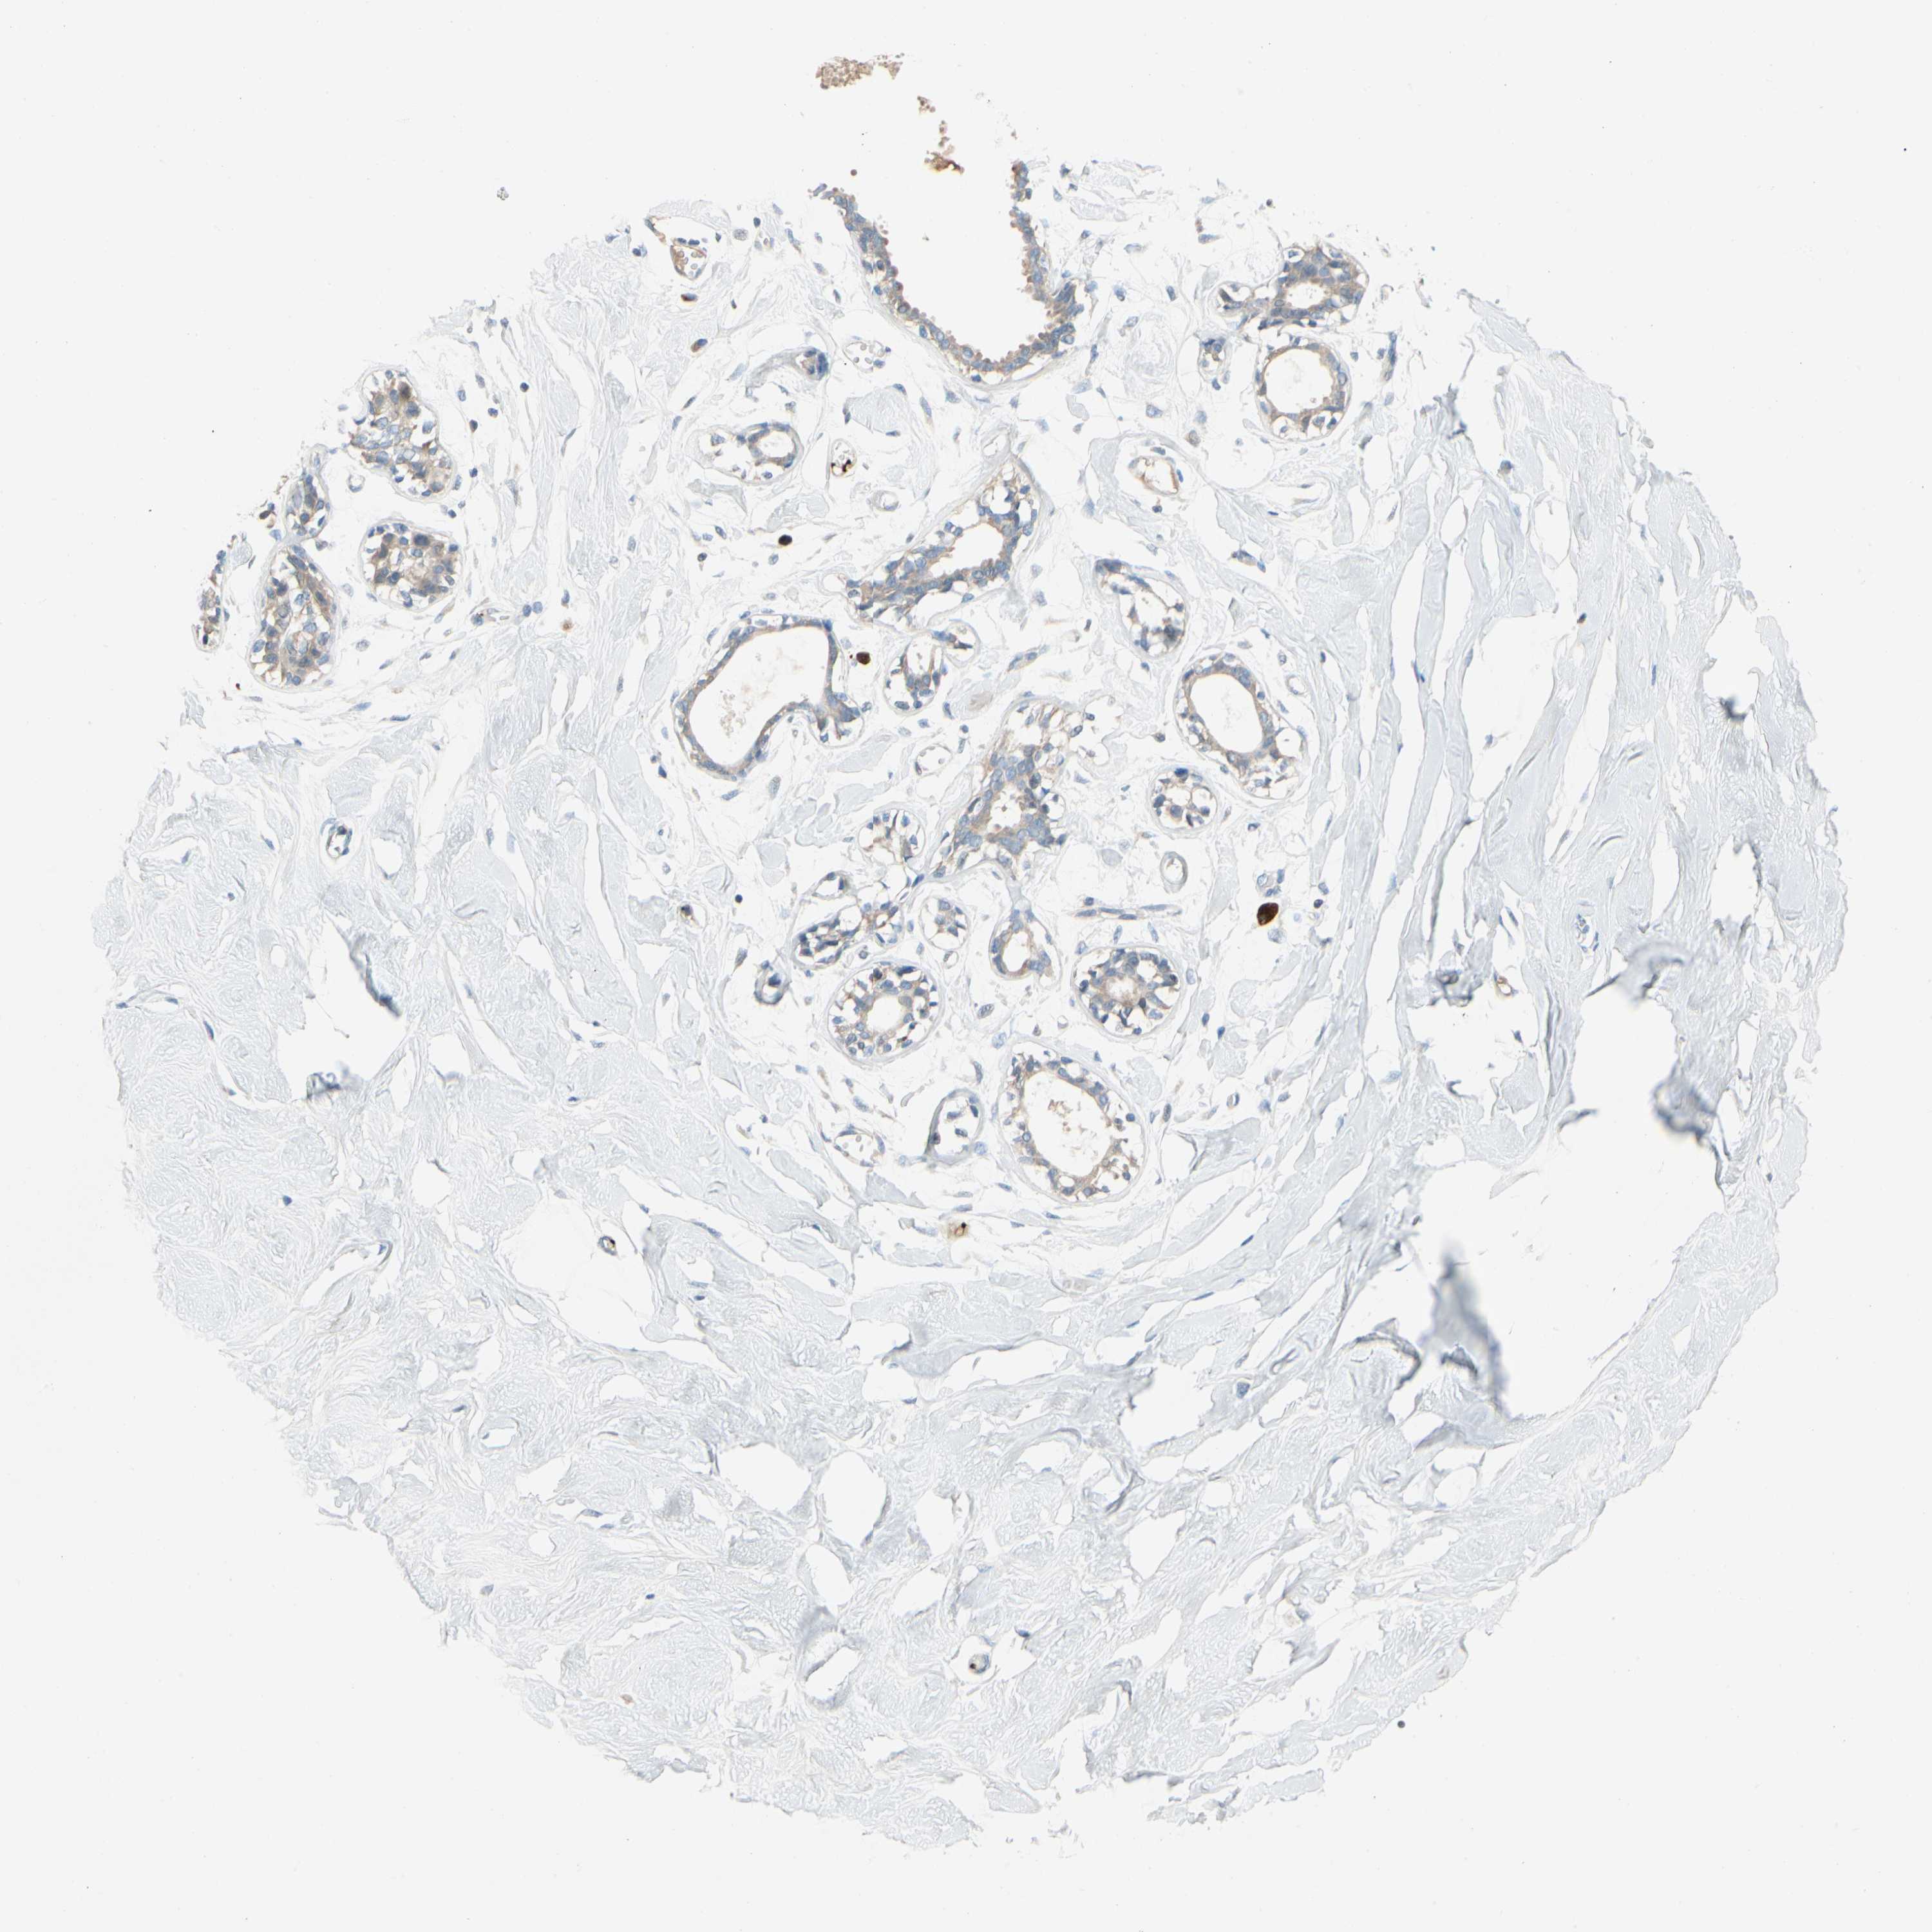

BREAST - Antibody stainingi

Antibody staining in the annotated cell types in the current human tissue is reported as not detected, low, medium, or high, based on conventional immunohistochemistry profiling in selected tissues. This score is based on the combination of the staining intensity and fraction of stained cells.

Each image is clickable and will lead to virtual microscopy that enables deeper exploration of all samples and also displays staining intensity scores, fraction scores and subcellular localization as well as patient and tissue information for each sample.

Antibody HPA008354Antibody CAB017624

Adipocytes Not detectedNot detected

Glandular cells LowNot detected

Myoepithelial cells Not detectedNot detected